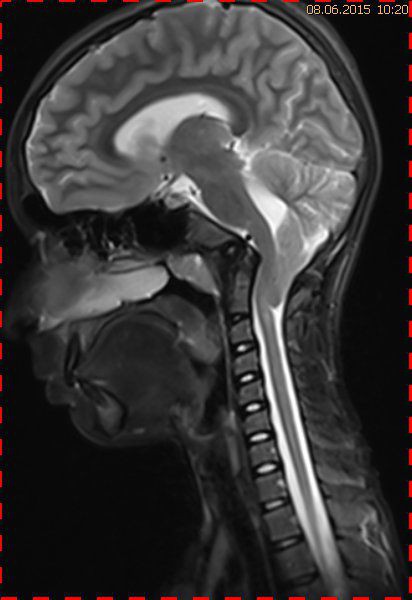

Abb. 2.1 Sagittales MRT (T2 TSE, 1,5 T): bei unveränderter Streckfehlhaltung der HWS 2 Monate nach der Erstuntersuchung Progredienz des Tonsillentiefstands, Syringomyelie

Trotz weiterer Schmerz- und Physiotherapie konnte keine Beschwerdereduktion erreicht werden. 2 Monate später erfolgte eine MRT des Kopfes zum Ausschluss einer posttraumatischen Veränderung.

Bei dieser Untersuchung wurde übersehen, dass die Kleinhirntonsillen in das Foramen magnum disloziert waren und eine Arnold-Chiari-Malformation mit Erweiterung des 4. Ventrikels und des Aquäduktes inklusive Kleinhirntonsillentiefstand vorlag. Bei zwischenzeitlich auswärtig erfolgtem CT der HWS wurde eine Anlagestörung im kraniozervikalen Übergang beschrieben. Eine Kontrolluntersuchung des Kopfes weitere 4 Monate später dokumentierte neben einem medullären Ödem einen progredienten Tonsillentiefstand, der zur neurochirurgischen Behandlung mit operativer Erweiterung des Foramen magnum führte.